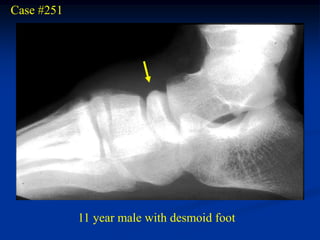

Case #251

11 year male with desmoid foot